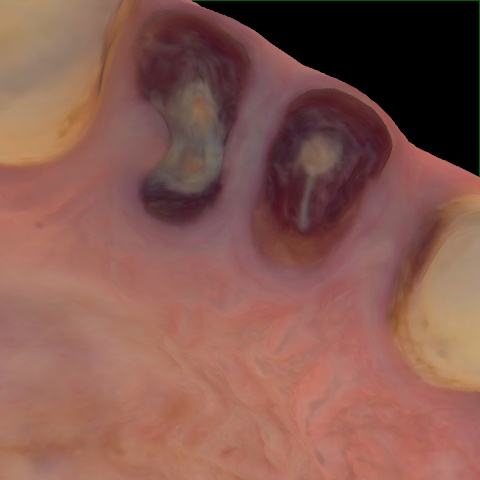

NHD36692

Annotated as "Good"